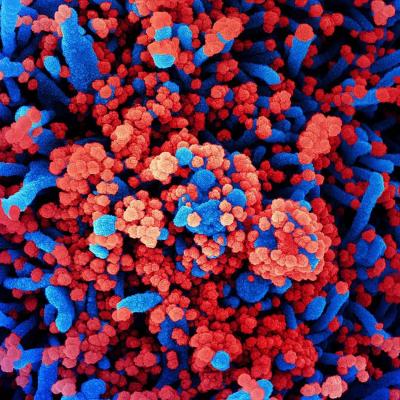

कोरोना व्हायरसने संपूर्ण जगभरात वर्षभरापासून हाहाकार पसरवला आहे. कोरोना व्हायरसच्या संक्रमणातून बाहेर आलेल्या लोकांसाठी एक नकारात्मक माहिती समोर येत आहे.

अमेरिकेतील टेक्सासमधील टेक युनिव्हर्सिटी ऑफ हेल्थ सेंटरच्या साहाय्याक प्राध्यापक डॉ. ब्रिटनी केंडेल यांनी केलेल्या दाव्यानुसार कोरोनावर मात केलेल्या लोकांना या आजाराच्या दीर्घकालीन परिणामांचा सामना करावा लागेल. तसंच त्यांची फुफ्फुसं स्मोकिंग करत असलेल्या लोकांच्या तुलनेत जास्त संवेदनशील होऊ शकतात.

यांनी सांगितले की, ''कोरोना पॉझिटिव्ह झाल्यानंतर तुमच्या फुफ्फुसांची स्थिती खूप खराब होऊ लागते. श्वास घेण्यासाठी त्रासाचा सामना करावा लागू शकतो. याशिवाय फुफ्फुसांच्या इतर समस्यांचा सामना करावा लागू शकतो.''

कोरोनाच्या संक्रमणानंतर फुफ्फुसांवर तीव्र परिणाम होण्याची शक्यता असते. हा आजार उद्भवल्यास रुग्णाला श्वास घ्यायला त्रास होतो. हळूहळू रुग्णांच्या शरीरात ऑक्सिजनची कमतरता भासायला सुरूवात होते. अनेकदा या लक्षणांची कारणं कळून येत नाहीत.या कंडीशनला डॉक्टरर्स इडियोपॅथिक पल्मोनरी फायब्रोसिस असं म्हणतात.(ImageCredit- Aajtak)